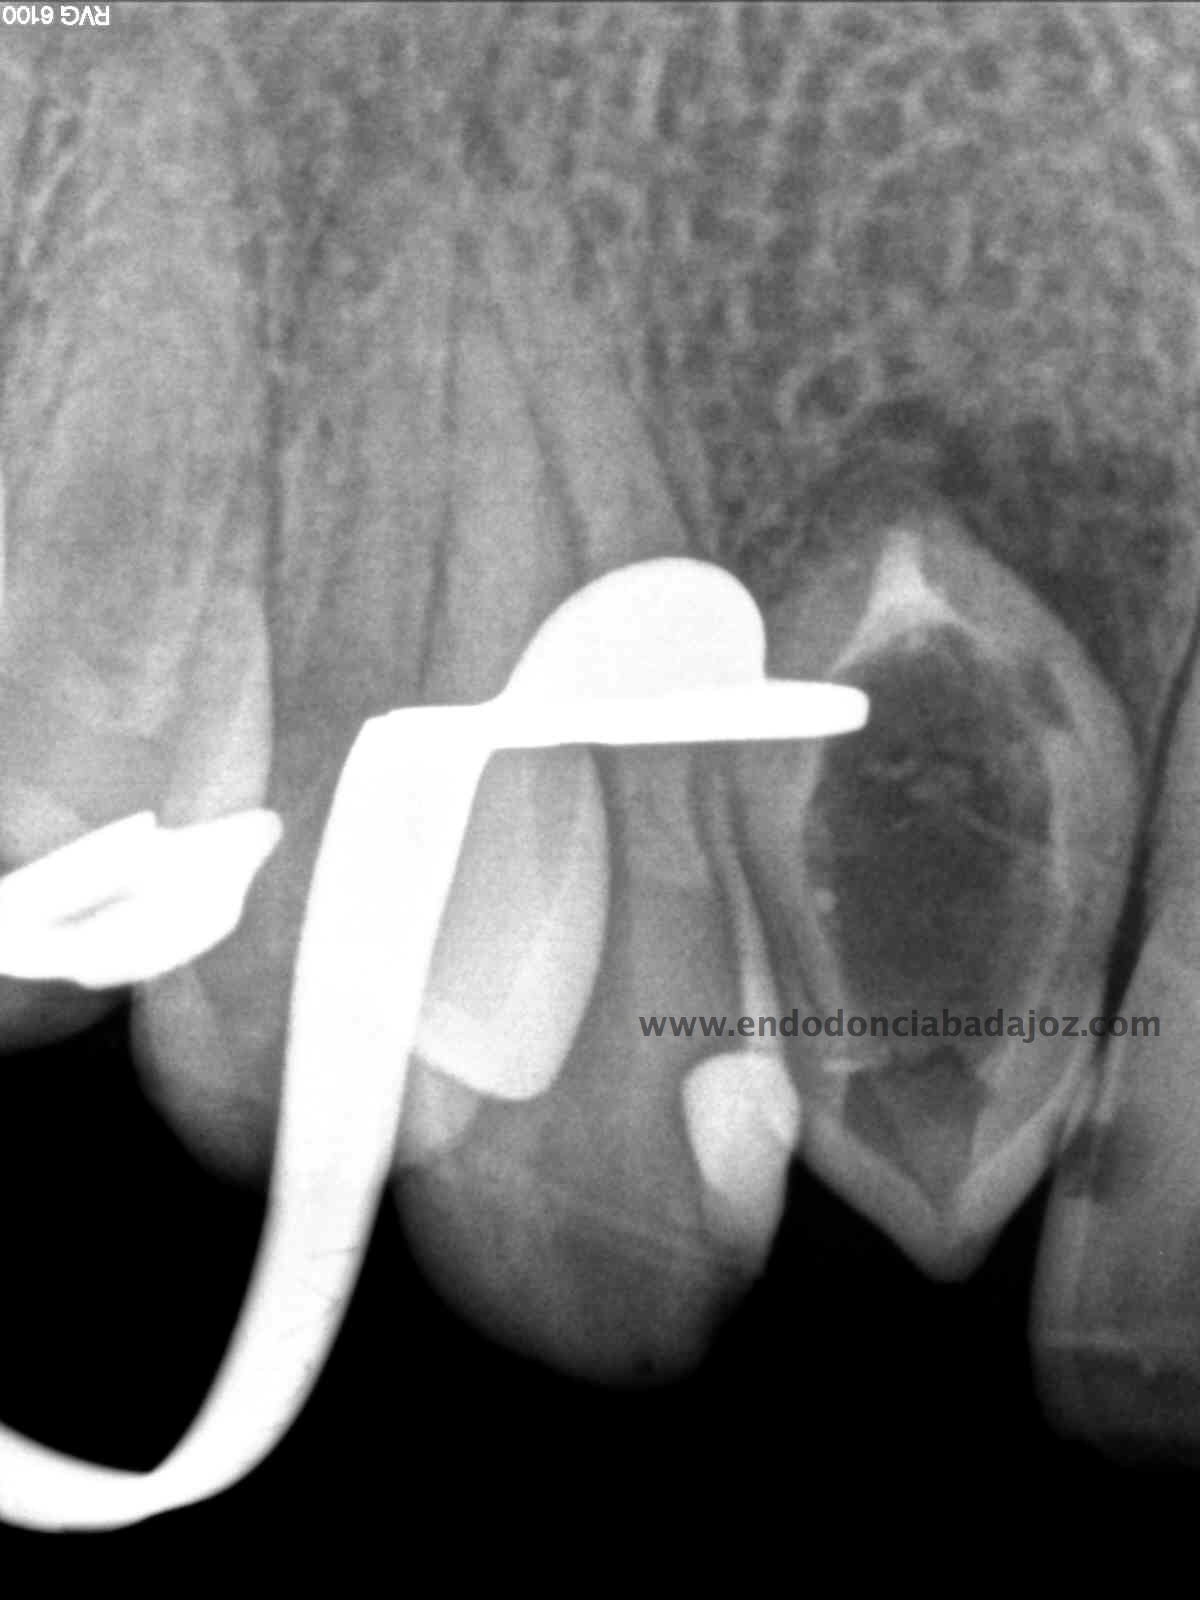

Nuestro caso, se trataba de esta pieza con necrosis pulpar con afectación periapical que presentaba una vía de drenaje (fístula). Esta radiografía muestra el camino de la fístula a la lesión apical.

Se planteó el caso con una apertura del mismo y tratamiento de todo el conducto con puntas de ultrasonido desbridando las paredes e intentando no eliminar demasiado tejido dentinario. El primer paso sería conseguir una permeabilización del conducto:

Como defensor del H de Ca ,en ciertas ocasiones, en este caso colocamos el mismo. En la siguiente cita, después de tallar el conducto, colocamos un sellado apical con cemento M.T.A. de varios milímetros y obturando con gutapercha inyectada con la pistola Obtura II.